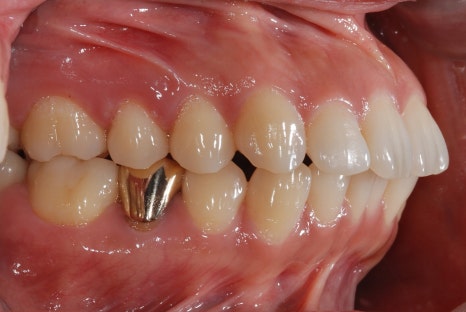

<Before-and-after orthodontic treatment photos>

Treatment period: 23.05.15 - 24.10.21 (about 1 year and 6 months)

Treatment performed: crowded teeth, alignment improvement